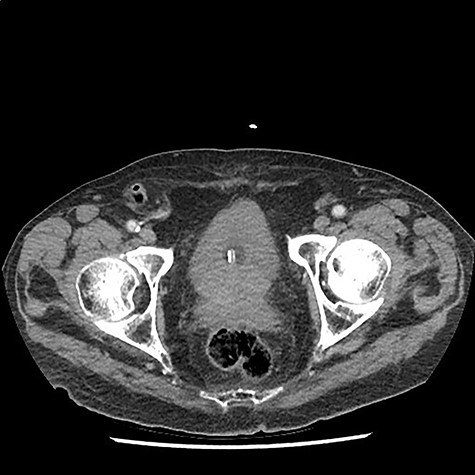

A 90 year old gentleman was admitted on the acute surgical take with right hypochondrium pain. On examination he was pyrexial, tachycardic markedly tender in the right upper quadrant of his abdomen. There was also a reducible non-tender right-sided inguinal hernia present. His past medical history included atrial fibrillation (anti-coagulated with apixaban) alongside ischaemic heart disease, osteoarthritis and a degree of congestive cardiac failure with poor exercise tolerance. On further questioning he had noticed the lump for several weeks but described no tenderness around the lump. Blood workup revealed c-reactive protein of 140 mg/L and white cell count of 15 × 109. He had mildly deranged renal function at baseline consistent with an element of chronic kidney disease. Other blood tests were unremarkable. A diagnosis of acute cholecystitis was made with an incidental finding of right-sided inguinal hernia. He was commenced on intravenous antibiotics and CT scan of the abdomen arranged to ensure no co-existent pathology given his age. CT scan revealed the presence of a right-sided inguinal hernia containing a thickened vermiform appendix with peripheral fat stranding suggestive of acute appendicitis within an Amyand’s hernia (Figs 1 and 2). Additionally, the scan did confirm the concurrent presence of acute uncomplicated cholecystitis. Senior surgical and anaesthetic discussions took place with regards to operating on this patient to treat his appendicitis and repair his hernia. It was universally agreed that the acute cholecystitis could be viably treated with intravenous antibiotics in the interim. However, acute appendicitis, with its risk of complications, warranted further discussion. Following discussion with the patient, consultant physicians, anaesthetists and surgeons, the decision was made to treat both conditions conservatively with antibiotics. The rationale for this was that the patient’s main complaint was that of right upper quadrant pain. He did not have any peritonism or tenderness to his right inguinal canal that would suggest impending perforation or peritonitis. His co-morbidities and age undoubtedly made him a high-risk case for appendicectomy and hernia repair. Most importantly, the patient himself was very reluctant to undergo operation and had full capacity to make this decision, having been made well aware of the risks of not intervening. Ultimately, following a 12 day stay with intravenous antibiotics, physiotherapy input and input from the physicians, he was discharged and to date has suffered no complications of his hernia or gallstone disease.

Coronal CT scan demonstrating appendicitis located within the inguinal canal.